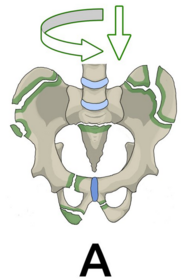

Typ B Beckenringverletzung mit rotatorischem Stabilitätsverlust mit inkompletter Durchtrennung des hinteren Beckenrings und erhaltener vertikaler Stabilität -> Partiell instabil. Beeinträchtigte Stabilität im hinteren Beckenring, Rotationsstabilität einer Beckenseite.

Was bedeutet rotationsinstabil? Bei Riss der Symphyse besteht Rotationsinstabilität, das heißt, dass bei horizontaler Krafteinwirkung die Beckenhälften unter Dehnung des Iliosakralgelenks auseinanderweichen.

Was sind Beispiele für Typ B? Nenne drei: Typ B1: Symphysensprengung ("open-book") Typ B2: Laterale Kompressionsverletzung Typ B3: Beidseitige B-Verletzung

Wie sehen Frakturen Typ A - C aus?